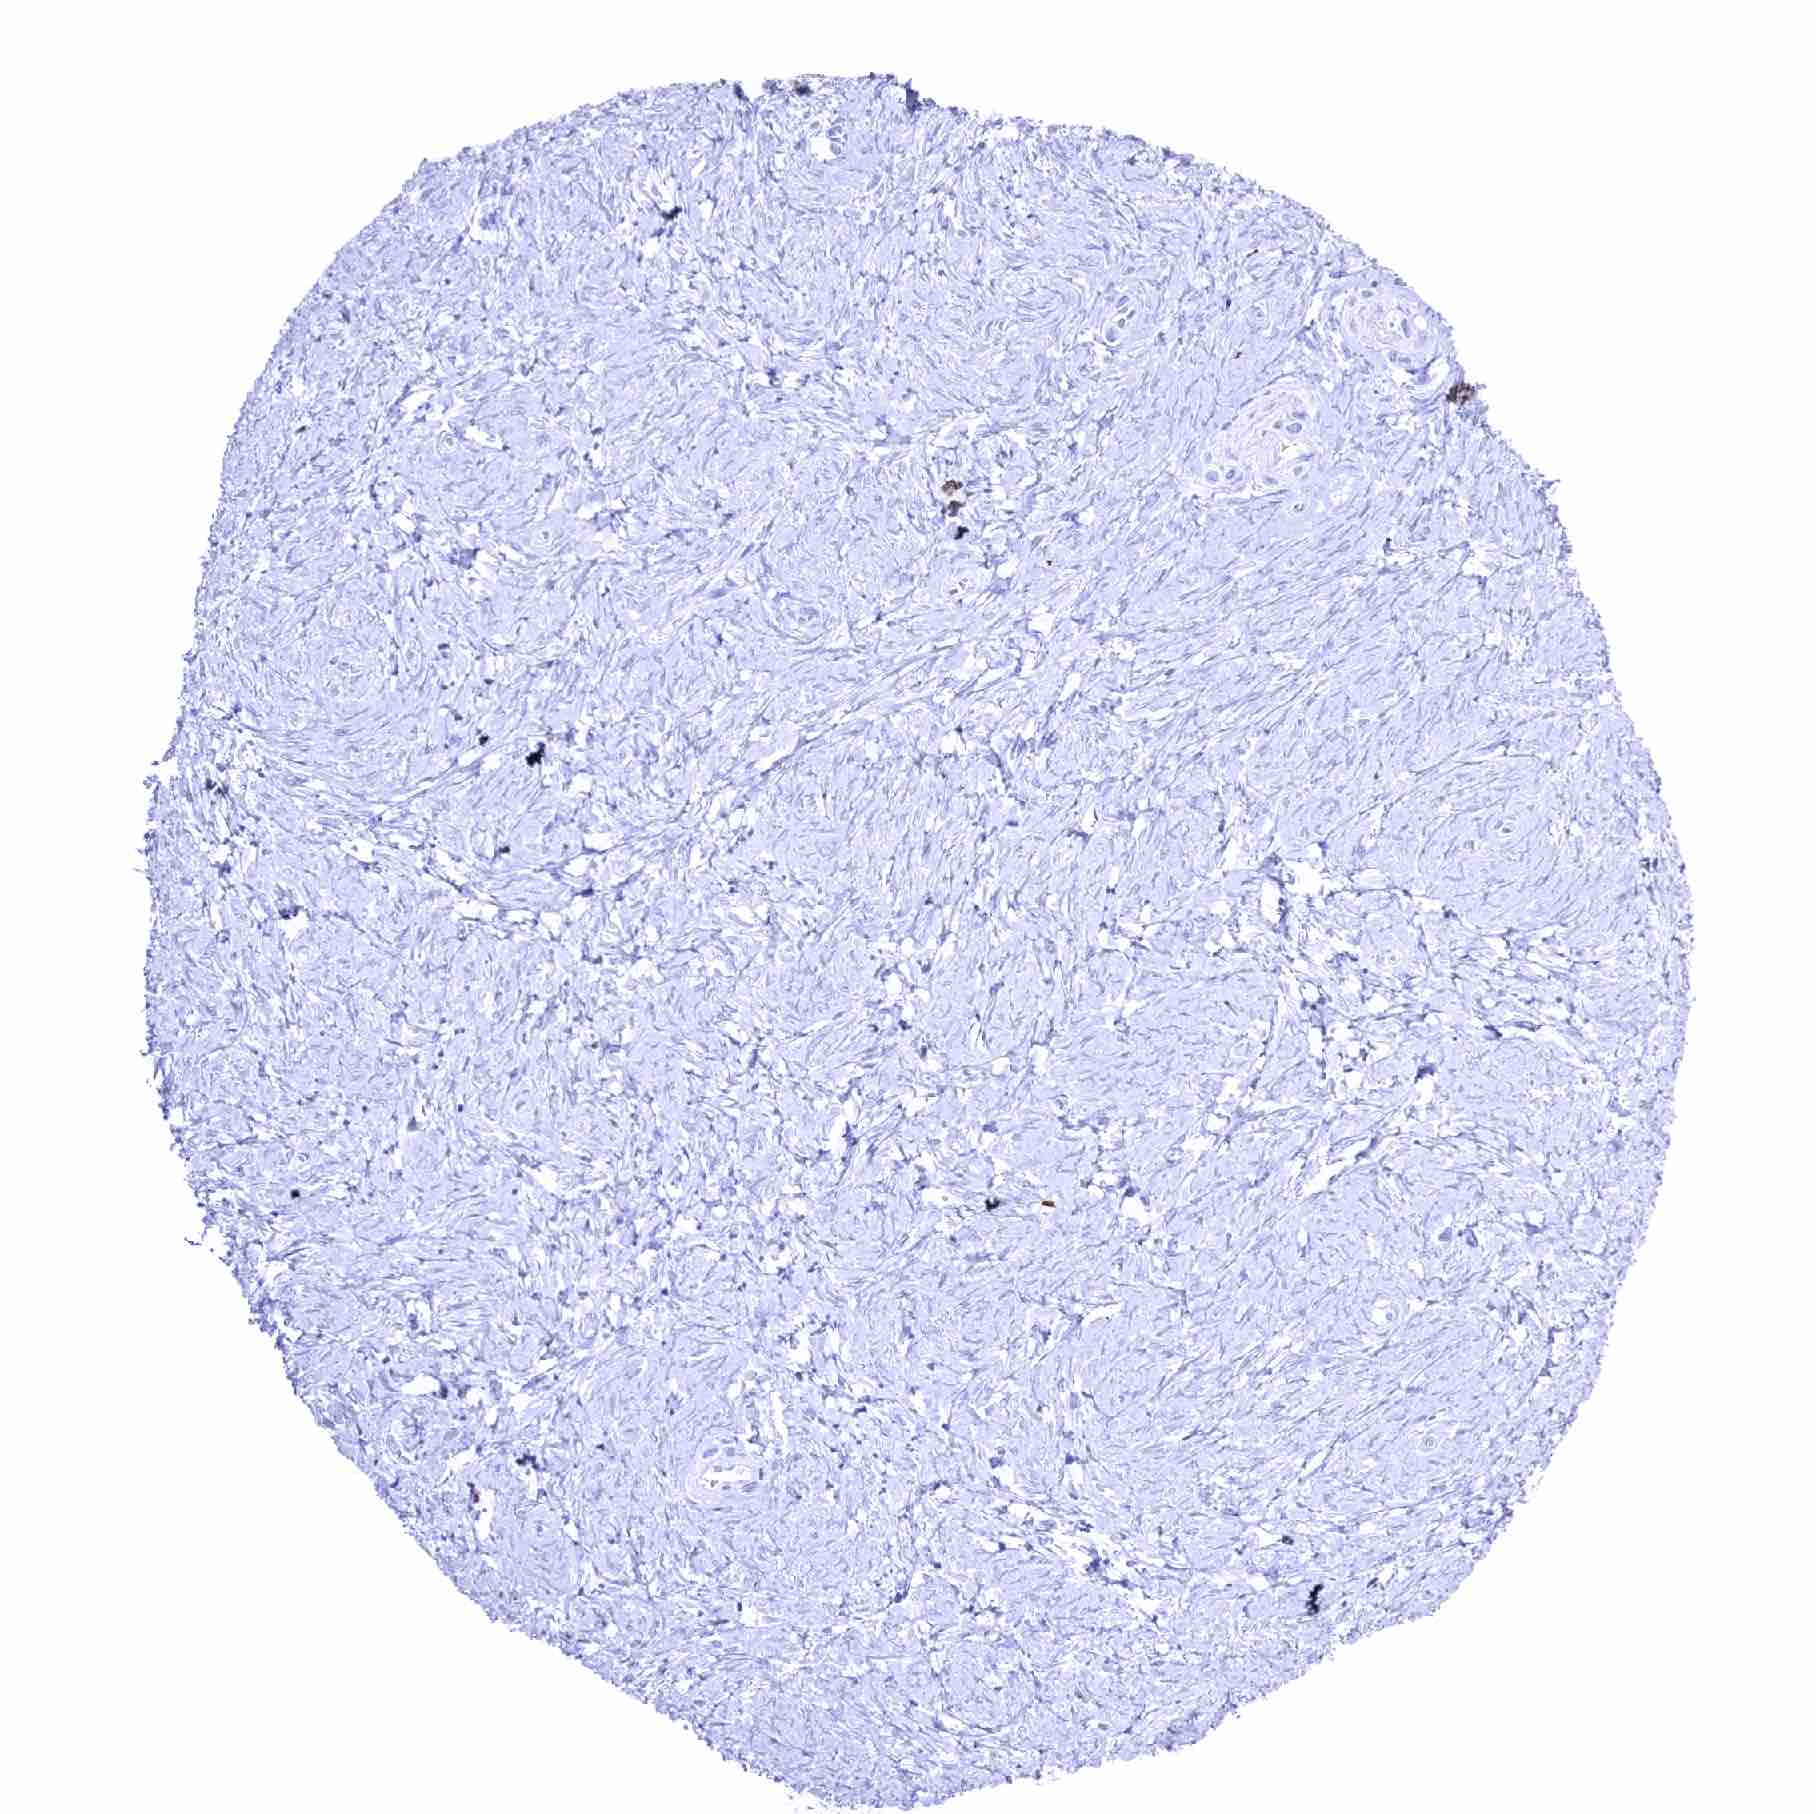

Prostate – Strong SOX2 positivity of a fraction of basal cells